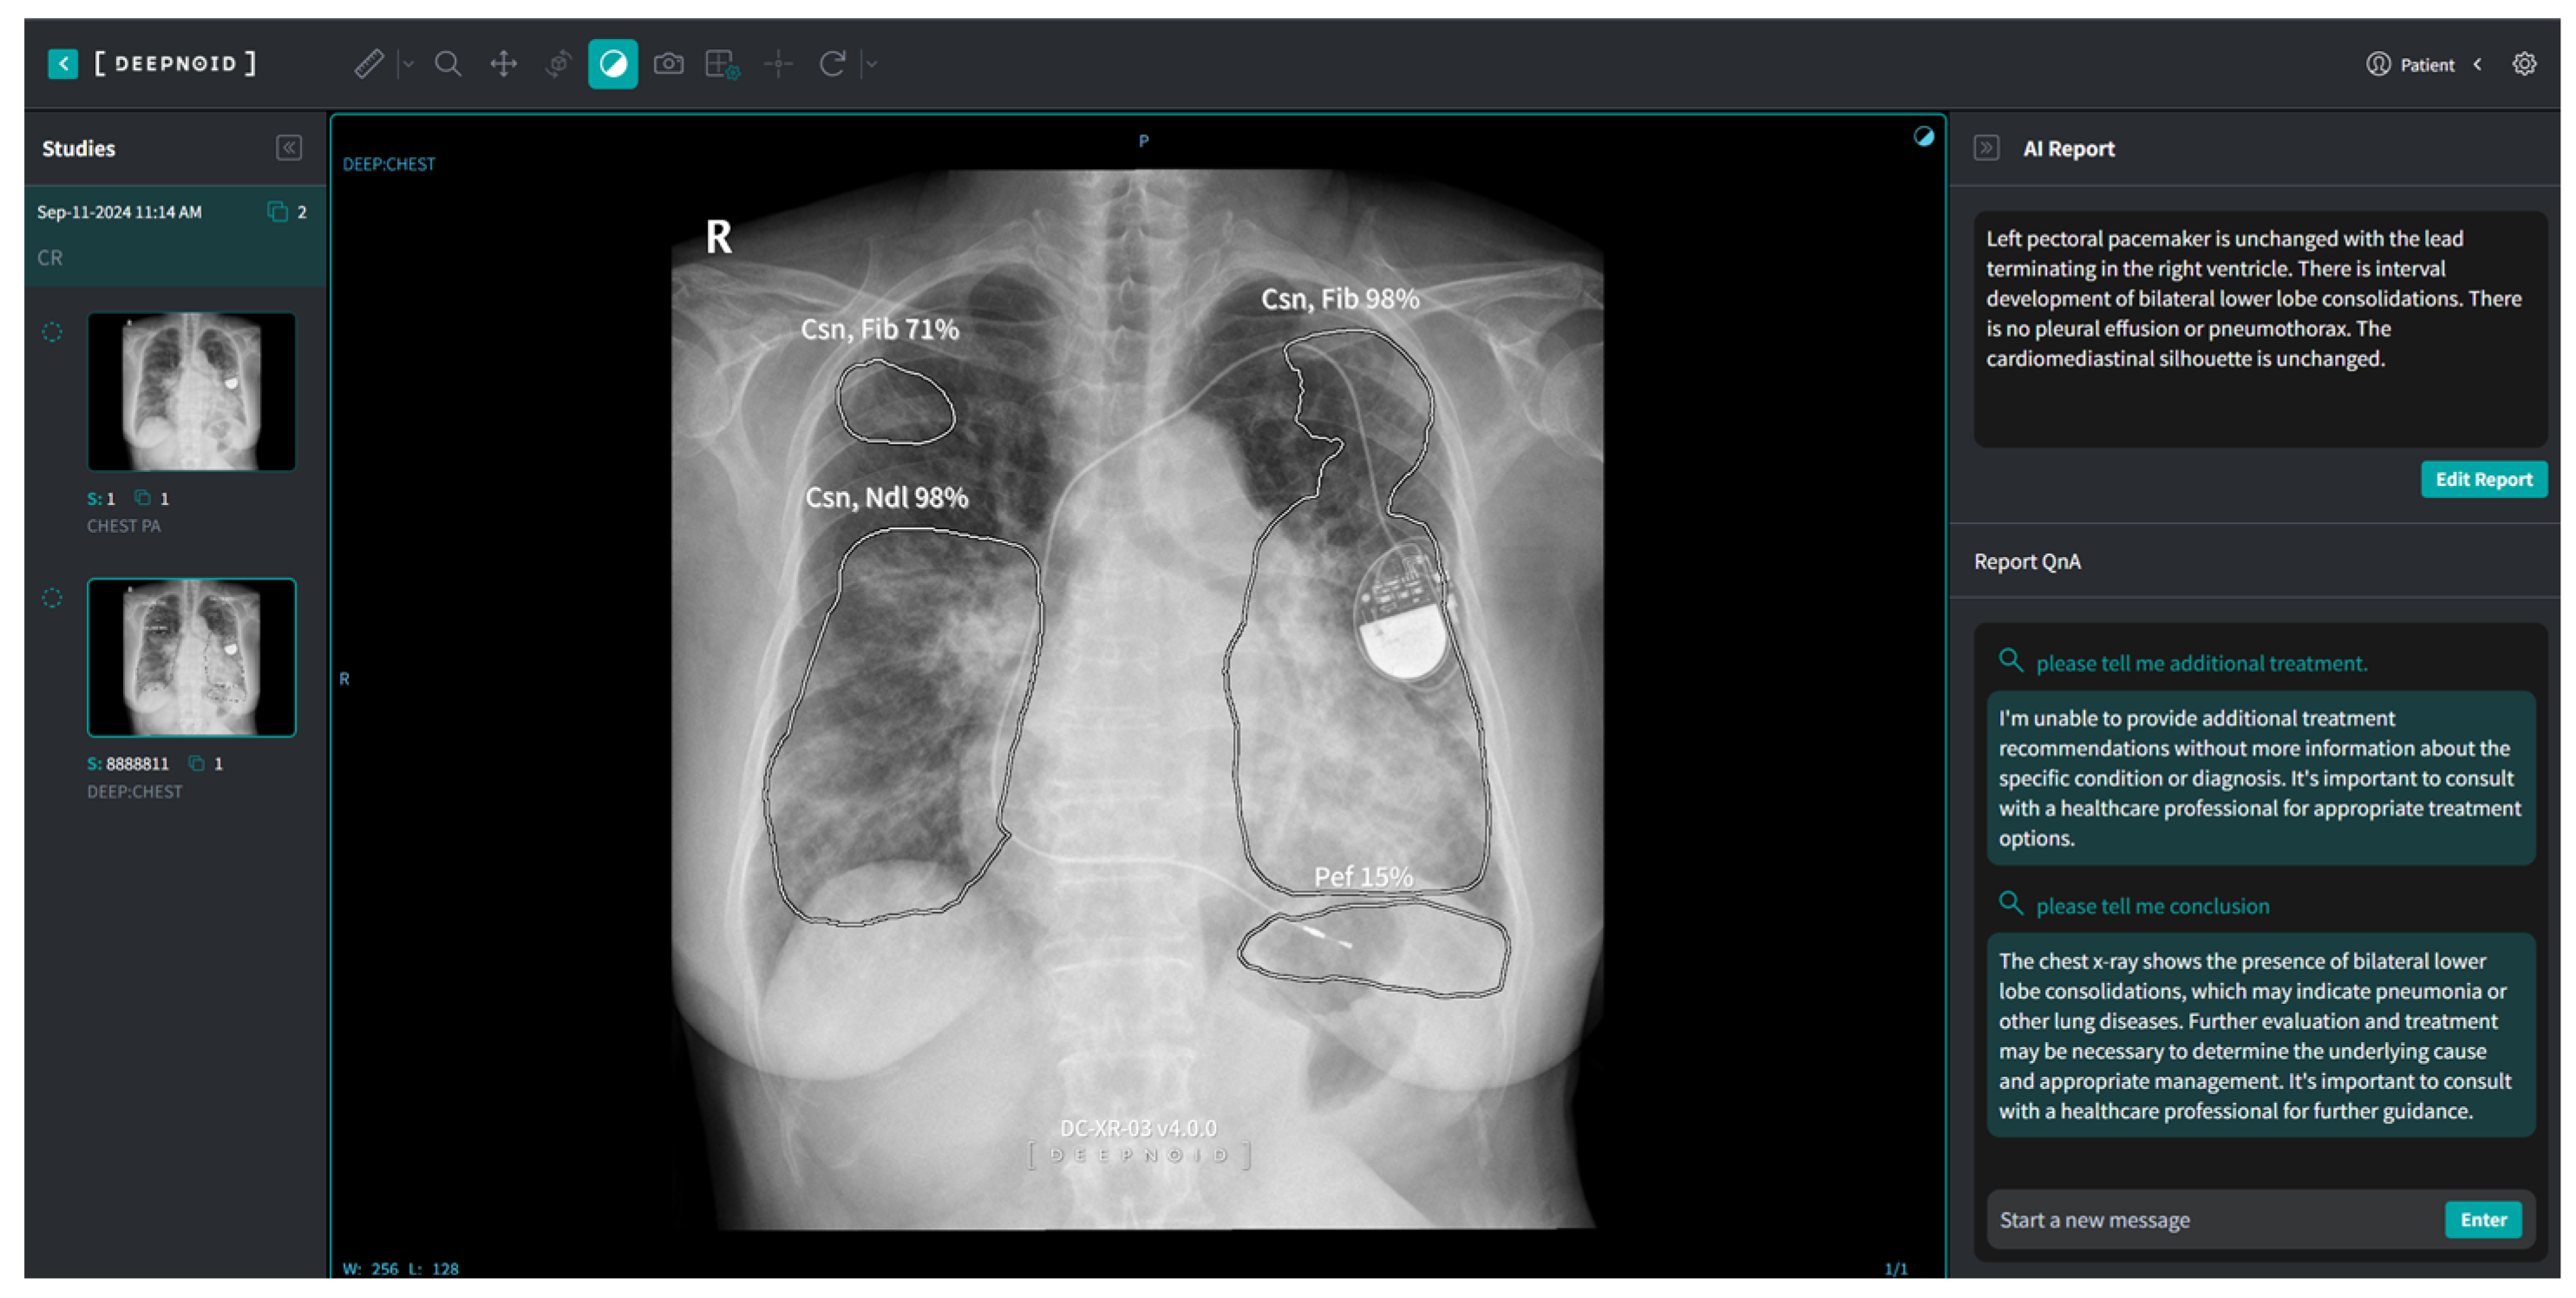

M4CXR, a cloud-based analytical platform, employs a transient data processing approach, wherein input DICOM data are immediately deleted post analysis to ensure data protection. The system generates text-based interpretations promptly upon DICOM file upload without requiring additional prompts. This study utilized a pre-release closed beta version of M4CXR (Figure 3), with public accessibility via web interface anticipated in February 2025.

Figure 3.

A schematic image of M4CXR in research use.